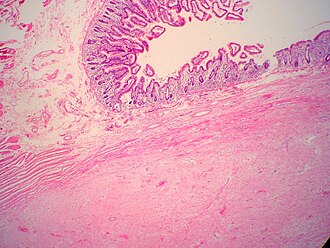

Desmoid-type fibromatosis. H&E stain. | |

| LM | "sweeping fascicles"/bundles, spindle cells with small slender nuclei, solid dark eosinophilic cytoplasm, +/-mitoses, long thin-walled vessels - parallel to one another |

- "Sweeping fascicles"/bundles.

- Spindle cells with:

- Small slender nuclei.

- Solid dark eosinophilic cytoplasm.

- +/-Mitoses - may be abundant.

- Long thin-walled vessels - parallel to one another - important feature.